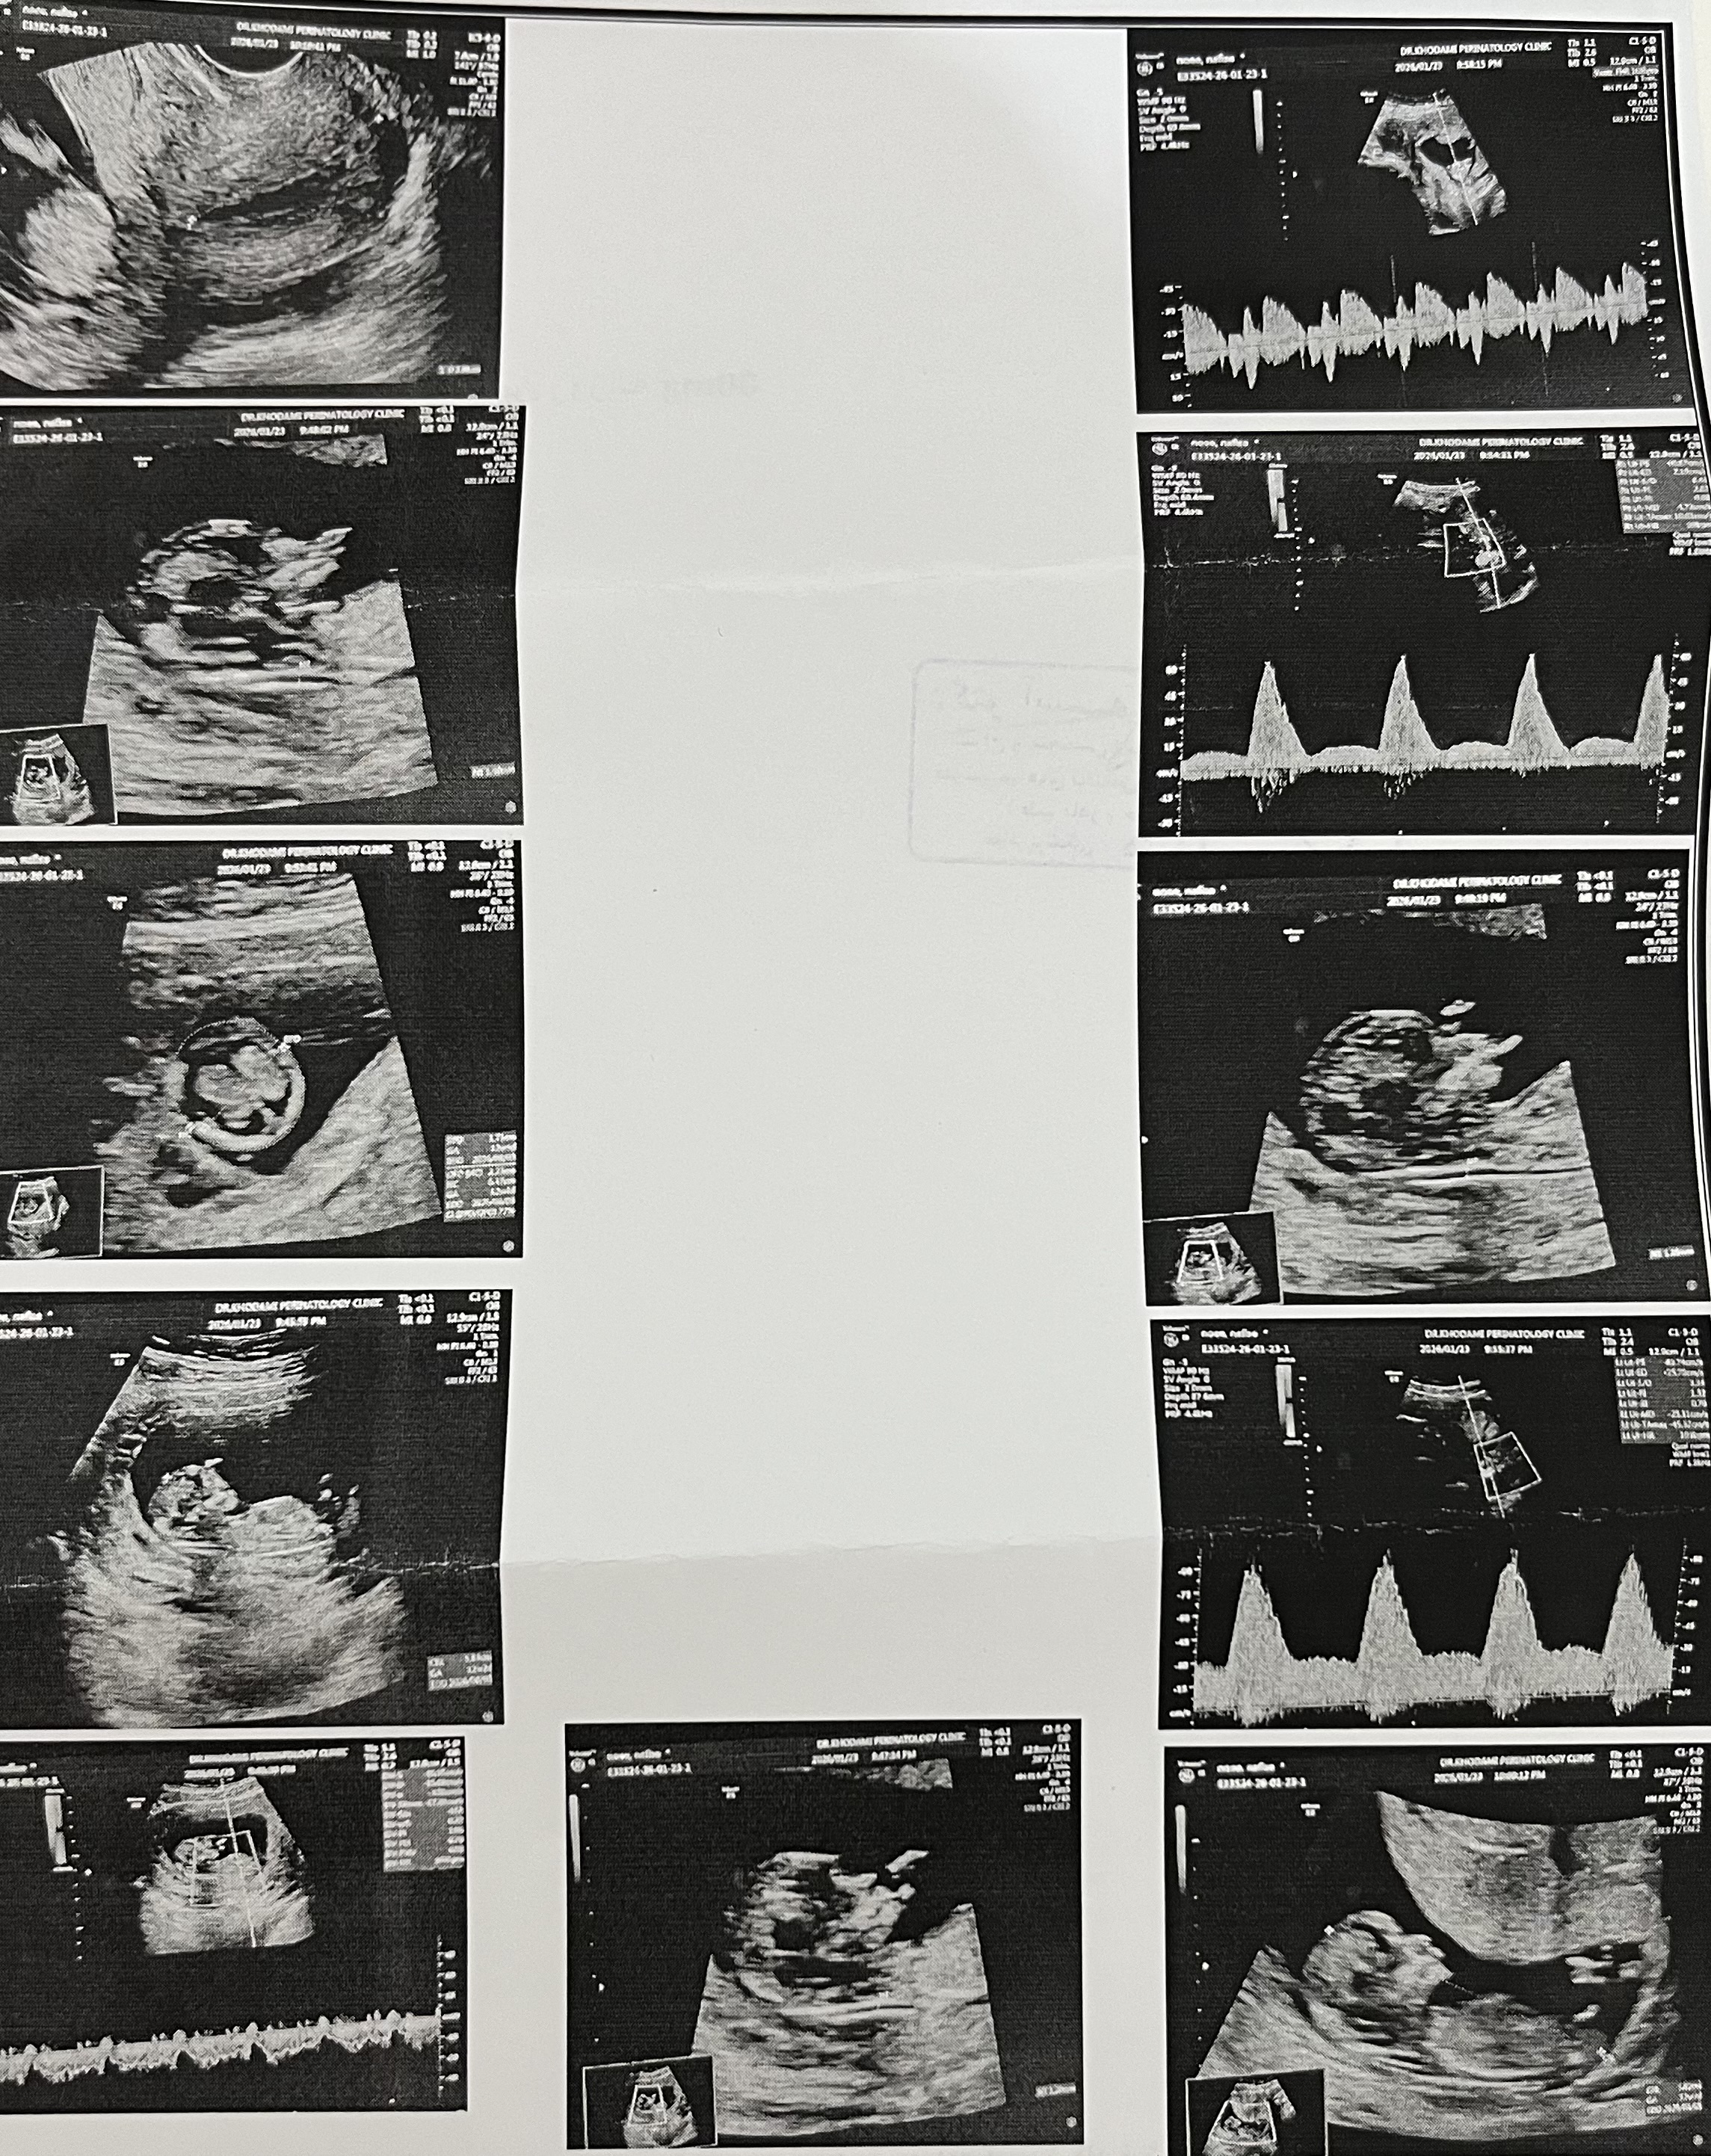

minmax27 مدیر استارتر عضویت: 1404/10/26 تعداد پست: 14 عنوان جنسیت بچه 40 بازدید | 14 پست این عکس از سونوی nt گرفتمراجع به جنسیت هیچی نگفت دکتر امروز | 16:17 0 نفر لایک کرده اند ... گزارش تاپیک نامناسب

minmax27 مدیر استارتر عضویت: 1404/10/26 تعداد پست: 14 عکس از برگ سونوگرافیت بده چند هفته انتی دادی ۱۲ هفته و دو روز

minmax27 مدیر استارتر عضویت: 1404/10/26 تعداد پست: 14 من متوجه نشدمچند هفته رفتی؟ ۱۲ هفته و دو رپز بودم

minmax27 مدیر استارتر عضویت: 1404/10/26 تعداد پست: 14 فک میکنم پسره حتی احتمال هم نداد بهت؟ ازش پرسیدمگفت نه مشخص نیستحتی دکتر خودم هم نشون دادم اونم گفت چیزی درمورد جنسیت بهت نگفت؟گفتم نهدکتر خودمم چیزی نگفت

minmax27 مدیر استارتر عضویت: 1404/10/26 تعداد پست: 14 من ۱۳ هفته رفتم انتی با قطعیت گفت بهم جنسیت رو منم الان ۱۳ هفته دو روزمهازمایش سلفری هم دادماونجا مشخص میشهالان یدفعه کنجکاو شدم😅

اهورامزداا عضویت: 1404/07/09 تعداد پست: 146 منم الان ۱۳ هفته دو روزمهازمایش سلفری هم دادماونجا مشخص میشهالان یدفعه کنجکاو شدم😅 چرا سلفری دادی؟ اره اونجا مشخص میشهمن الان ۱۹ هفتم اخر هفته تایم انومالی دارم

minmax27 مدیر استارتر عضویت: 1404/10/26 تعداد پست: 14 چرا سلفری دادی؟ اره اونجا مشخص میشهمن الان ۱۹ هفتم اخر هفته تایم انومالی دارم بخاطر سن۳۹ سالمهیبار هم سابقه سقط دارماین بارداری هم جفتم پایینهو چند بار هم لکه بینی داشتمایشالا همه چی خوب پیش بره برات😍برای منم دعا کن